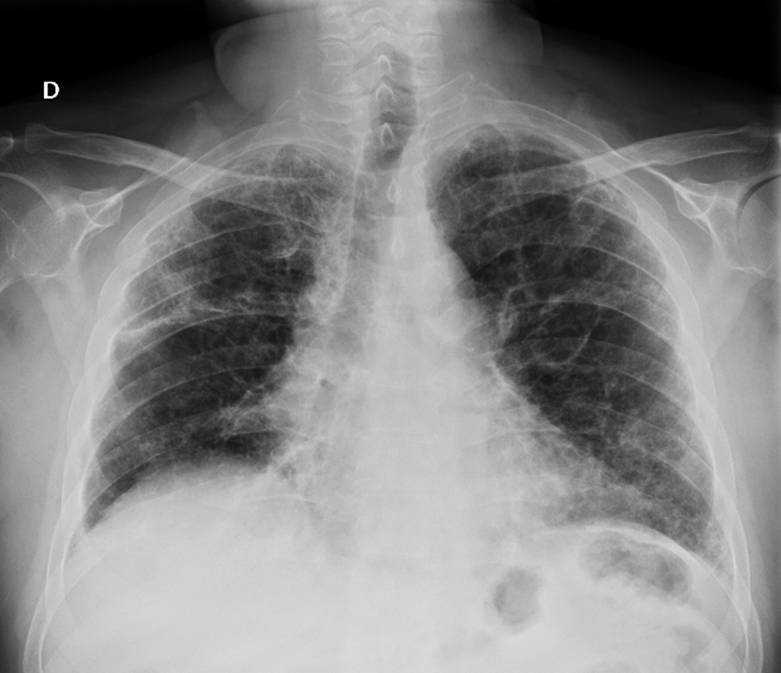

O fim de uma das doenças mais letais do mundo pode estar mais próximo. Pesquisadores das universidades de Oxford e University College London anunciaram o início dos testes em humanos da LungVax, a primeira vacina projetada para prevenir o câncer de pulmão em pessoas com alto risco de desenvolver a doença.

O anúncio marca um avanço potencial na luta contra o tipo de câncer que mais mata no Reino Unido. Ou seja, o responsável por 20% das mortes por câncer no país anualmente.